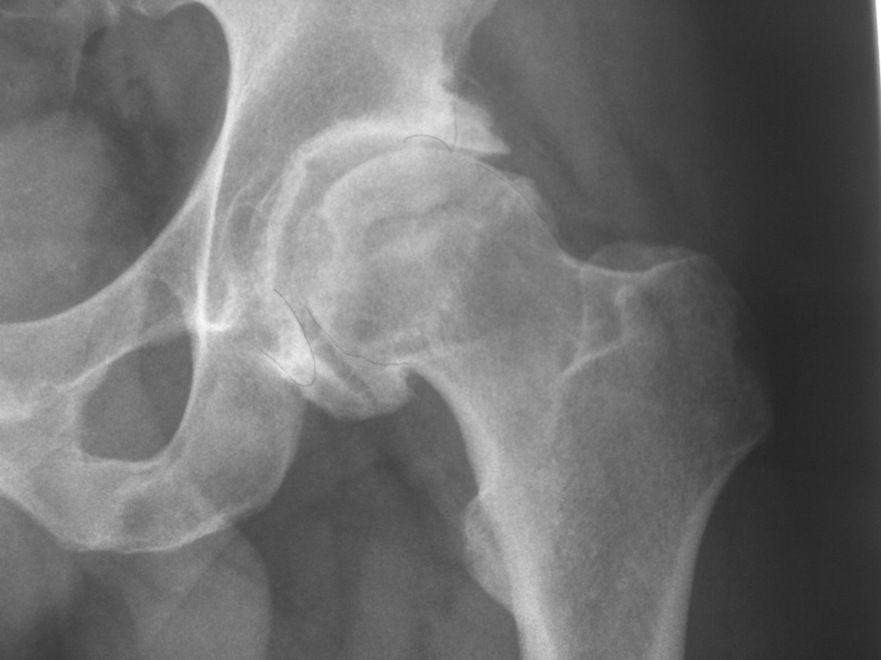

La Artrosis es una enfermedad degenerativa de las articulaciones. Consiste en la pérdida del cartílago articular, la formación de osteofitos y la deformación de la articulación afectada. Existen factores desencadenantes, como un traumatismo importante, y factores que aceleran la progresión de la artrosis, como la inestabilidad o la sobrecarga mecánica de la articulación. También existe una predisposición genética a padecer la enfermedad. La artrosis es habitual en articulaciones como la rodilla, la cadera, las articulaciones de las manos y la columna vertebral.

La artrosis de cadera es frecuente. Puede ser primaria o secundaria a diversas patologías. Entre las más frecuentes están la Luxación traumática de la cadera, la Necrosis avascular de la cabeza del fémur, las Epifisiolisis de la cabeza del fémur, la Enfermedad de Perthes o la Displasia del desarrollo de la cadera.

La artrosis de cadera se caracteriza por el dolor en relación con la actividad, sobre todo en la región inguinal, y la disminución de la movilidad de la misma. Además pueden existir crujidos y pérdida de fuerza en la pierna. Si es avanzada es habitual la cojera.